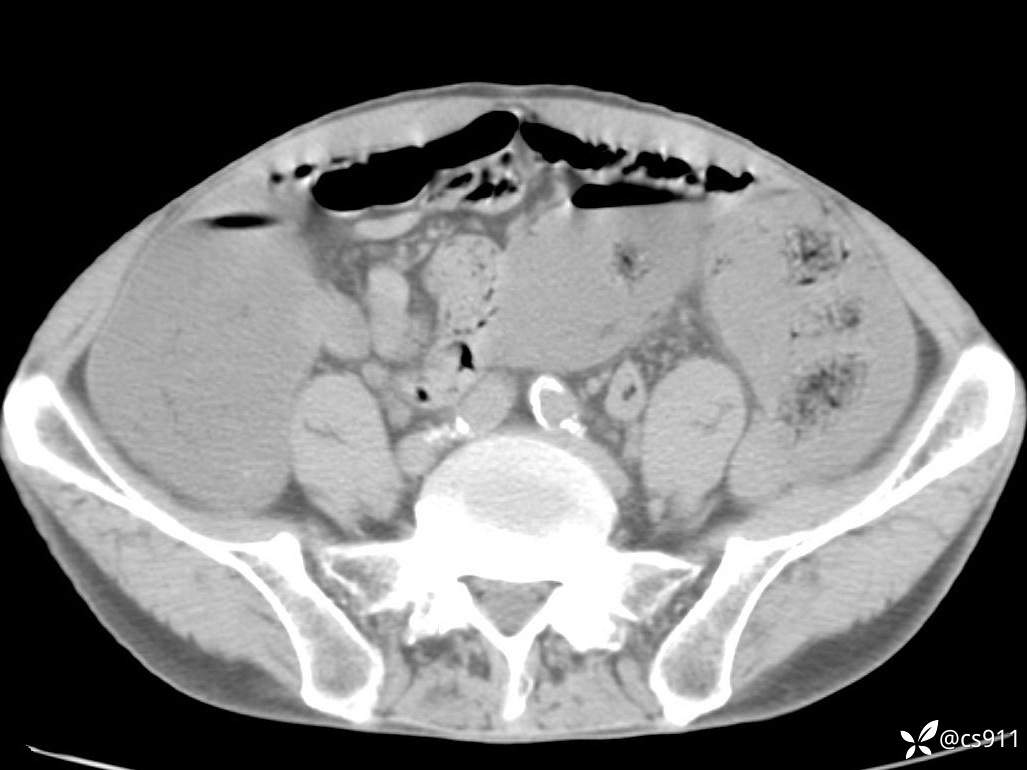

急腹症之急诊CT,原因?答案公布

男,77岁,腹痛、腹胀伴恶心呕吐1天。呕吐胃内容物,非喷射性呕吐,有咖啡色样胃内容物,诉有胃穿孔病史。查体:全腹平,下腹部压痛,全腹无反跳痛,叩诊呈浊音,移动性浊音阴性,肠鸣音减弱,1-2次/分。肛检:直肠未扪及明显肿物,可触及大量粪块。

T 36.6℃ P 80次/分 R 26次/分 BP 100/60mmHg

白细胞(WBC) H 14.55 10e9/L 4-10

中性粒细胞百分率(NEUT%) H 85.7 % 40-75

血淀粉酶(AMY) HH 1859 U/L 35-135

癌胚抗原(CEA) H 27.44 ng/ml 0-5

呕吐物 潜血试验 * 阳性 阴性

患者轮椅入室检查神志清楚, 能配合摆位和呼吸